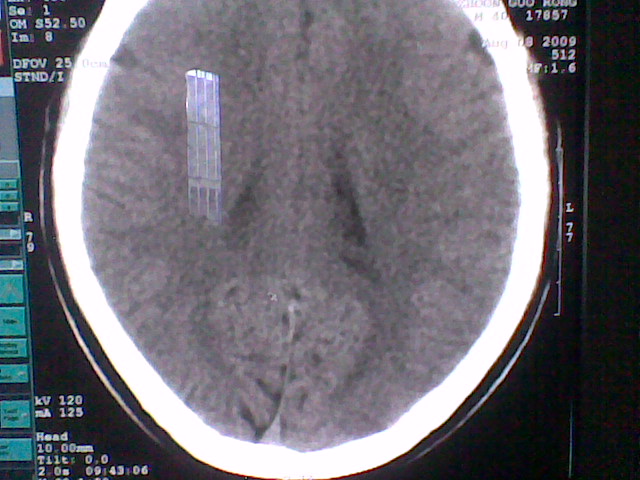

患者,男,头晕4天来诊,要求ct。

大枕大池合并蛛网膜囊肿。

支持 大枕大池合并蛛网膜囊肿。

考虑大枕大池合并蛛网膜囊肿。

有没有dandy-walker综合征的可能?